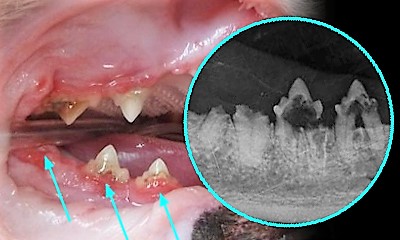

Зовні зуби при цьому можуть не відрізнятися від здорових і діагноз може бути поставлений тільки на підставі стоматологічного рентгена у ветеринарній клініці. Якщо ви помітили у свого улюбленця локальні ділянки гінгівіту, почервоніння ясен біля окремих зубів (особливо це стосується премолярів на нижній щелепі, які розташовані одразу за іклами) — це привід показати кішку ветеринарному лікарю. Саме треті премоляри на нижній щелепі (які зовні можна назвати першими, адже розташовані вони відразу після іклів) є зубами-маркерами резорбції. Якщо ураження є на цих зубах, згодом його слід очікувати й на інших.

Фото резорбції зубів у кішок: посилання на фото1, фото2, фото3. Чутливий контент.